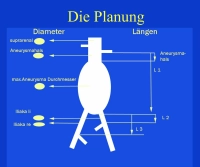

- anatomia inadequada para EVAR: zona de ancoragem, colo do aneurisma (ângulo, comprimento), vasos ilíacos (estenoses, alongamento, torção), trombos, calcificação

EVAR requer vasos ilíacos adequados para acesso, pois os sistemas de stent graft são frequentemente de grande calibre. Problemáticos são vasos ilíacos ateroscleróticos estreitados, tortuosos e torcidos, mas também dilatados aneurismaticamente.

- AAA infrarrenal, diâmetro 54,2 mm

- aneurisma da artéria ilíaca comum direita, diâmetro 41,1 mm